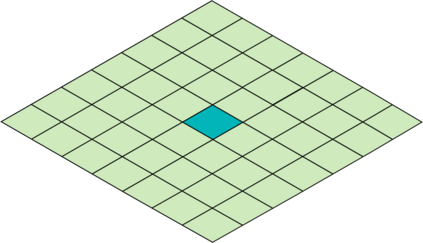

Deep Convolutional Neural Networks (DCNNs) are used extensively in biomedical image segmentation. However, current DCNNs usually use down sampling layers for increasing the receptive field and gaining abstract semantic information. These down sampling layers decrease the spatial dimension of feature maps, which can be detrimental to semantic image segmentation. Atrous convolution is an alternative for the down sampling layer. It increases the receptive field whilst maintains the spatial dimension of feature maps. In this paper, a method for effective atrous rate setting is proposed to achieve the largest and fully-covered receptive field with a minimum number of atrous convolutional layers. Furthermore, different atrous blocks, shortcut connections and normalization methods are explored to select the optimal network structure setting. These lead to a new and full-scale DCNN - Atrous Convolutional Neural Network (ACNN), which incorporates cascaded atrous II-blocks, residual learning and Fine Group Normalization (FGN). Application results of the proposed ACNN to Magnetic Resonance Imaging (MRI) and Computed Tomography (CT) image segmentation demonstrate that the proposed ACNN can achieve comparable segmentation Dice Similarity Coefficients (DSCs) to U-Net, optimized U-Net and hybrid network, but with significantly reduced trainable parameters due to the use of full-scale feature maps and therefore computationally is much more efficient for both the training and inference.